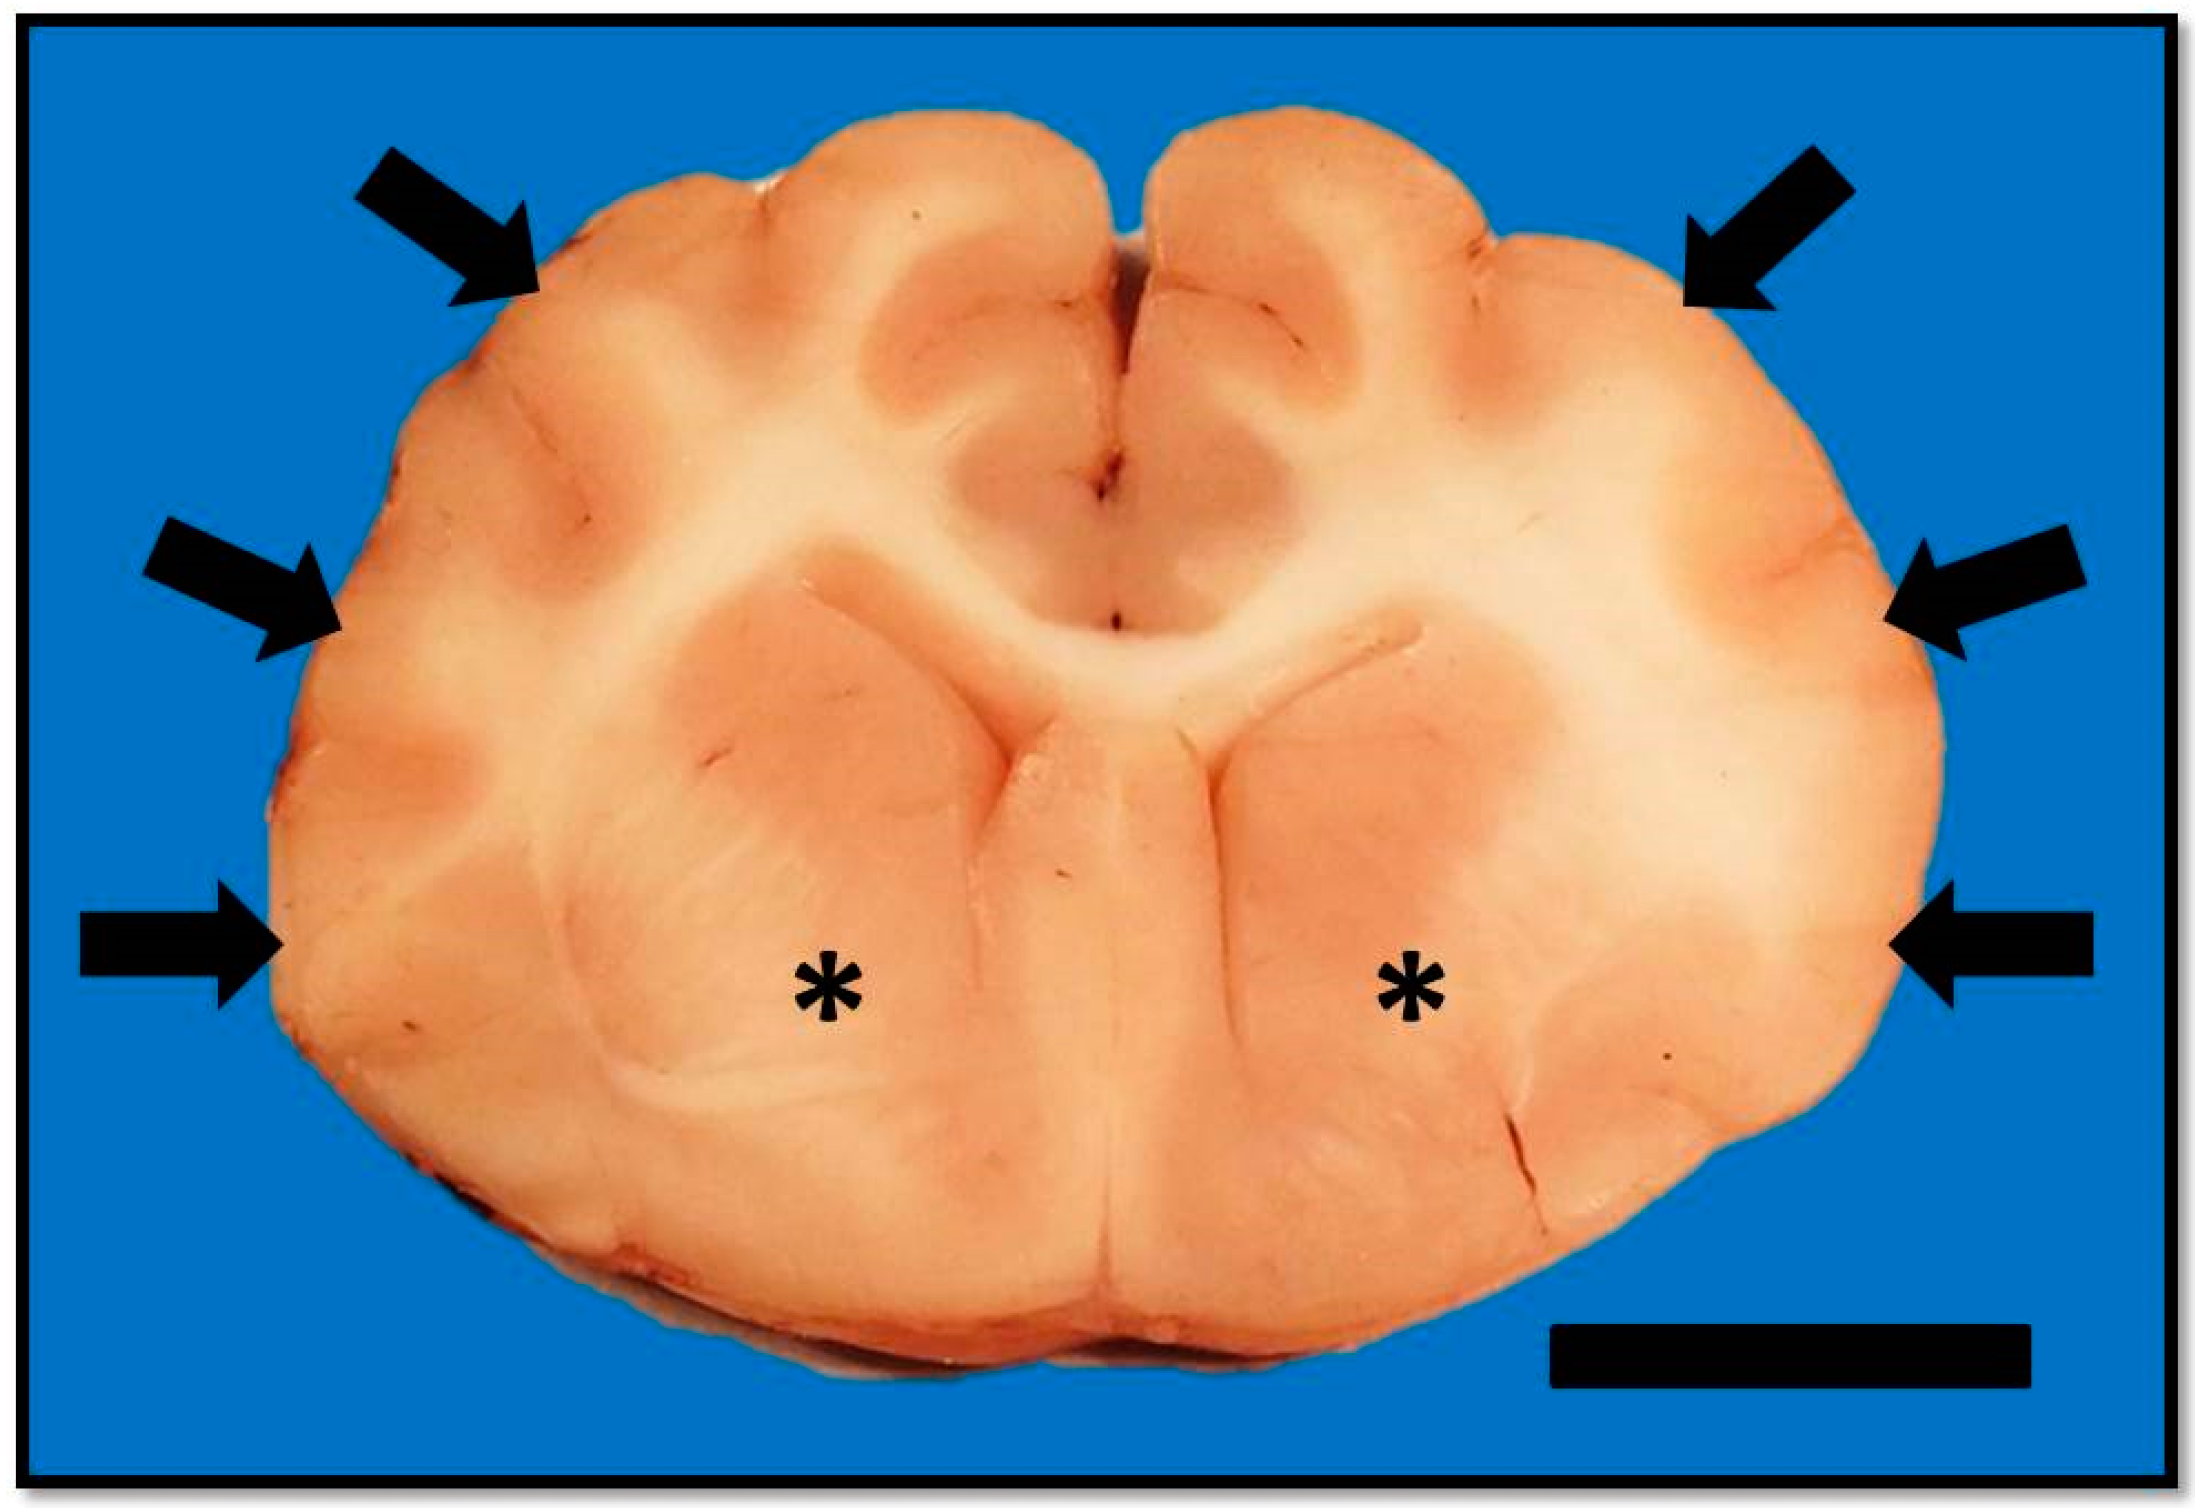

On MRI scanning of the brain, an intra-axial, diffuse, non-contrast-enhancing, T2-weighted, hyperintense mass effect extending through the ventral forebrain (including the piriform and temporal lobes, thalamus, crus cerebri, and colliculi) and midbrain (Figure 1) was found. The caudal aspects of the cerebellum were compressed against the occipital bone. There was also caudal transtentorial herniation of the midbrain and herniation of the cerebellar vermis through the foramen magnum (Figure 2). A linear, T2 hyperintense area was present in the dorsal aspect of the C2-C5 spinal cord; transverse images of this area showed dilation of the central canal, T2 hyperintensity, and non-contrast-enhancing T1 hypointensity in the dorsal spinal cord, most consistent with syrinx formation. Based on clinical findings and MRI results, differential diagnoses included multicentric neoplasia or an infectious etiology such as feline infectious peritonitis (FIP), feline immunodeficiency virus (FIV), feline leukemia virus (FeLV), or cryptococcosis. Due to poor prognosis and rapid clinical decline, the cat was humanely euthanized.

Figure 1. T2 weighted transverse image at the level of the piriform lobe showing the ill-defined, ventrally distributed T2-weighted hyperintensity affecting the piriform lobes, temporal lobes, hypothalamus, and portions of the caudal colliculus and internal capsule (arrows). MRI scan.